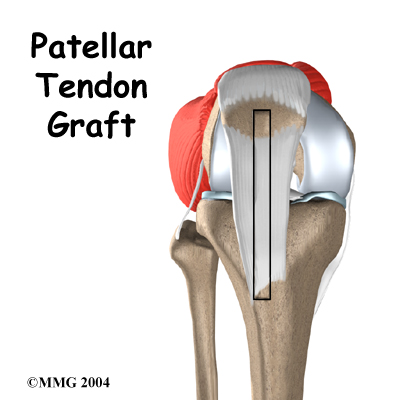

Patella Stabilization Surgery MPFL Reconstruction Surgery 2025, Patellar Fractures Broken Kneecap OrthoInfo AAOS 2025, Patellar Fractures Broken Kneecap OrthoInfo AAOS 2025, Patella Fracture treatment Patella Fracture surgery 2025, Patella Fracture Repair 2025, Surgical Technique for Chronic Proximal Patellar Tendinopathy 2025, Patella tendon harvest for ACL reconstruction Surgical Technique 2025, Quadriceps Repair and Patellar Tendon Tear Surgery Hoag 2025, Preoperative X rays of a comminuted patella fracture above . 3 2025, Knee Fracture Surgery Boulder City Total Knee Joint Replacement 2025, Frontiers A New Antirotation Strategy of K Wire Tension Band 2025, Lateral Release Knee Surgery Recovery Knee Pain Explained 2025, Patella Tendon Injury Symptoms Treatment Recovery Time 2025, A different unhappy triad in the knee a case of acute 2025, Patellar Tendon Rupture Treatment Management Approach 2025, Patella Injury Treatments Knee Surgeons Consultants Yorkshire 2025, Right Patellar Surgery Trial Exhibits Inc 2025, Physiotherapy in River Heights Winnipeg for ACL Patellar Tendon 2025, ACL Reconstruction Patellar Tendon Graft Technique 2025, Patellar Tendon Tear OrthoInfo AAOS 2025, Patella Knee cap Joint surgeon 2025, ACL Reconstruction Patellar Tendon Video Knee Surgery Videos 2025, Patellar knee cap dislocation correction Knee Hip and Shoulder 2025, Comparison of a minimally invasive surgical technique with open 2025, Patella Fracture Treatment Leicester UK Kneecap Fracture 2025, Patellar Fractures Broken Kneecap OrthoInfo AAOS 2025, What You Need to Know About Kneecap Injuries Sports health 2025, Patella Tendinopathy also known as Jumper s Knee Complete Physio 2025, Knee Replacement Surgery Details Recovery 2025, Congenital Dislocation of the Patella Surgical Reconstruction 2025, Ligament augmentation reconstruction system artificial ligaments 2025, Patellar Tendonitis Jumper s Knee Johns Hopkins Medicine 2025, Patella Fracture Orthopaedic Trauma Association OTA 2025, Knee Surgery Troy Knee Injury Treatment Knee Surgeon Rochester 2025, Patellar tendon repair performed in a right knee. After a well 2025.

Patella Stabilization Surgery MPFL Reconstruction Surgery 2025, Patellar Fractures Broken Kneecap OrthoInfo AAOS 2025, Patellar Fractures Broken Kneecap OrthoInfo AAOS 2025, Patella Fracture treatment Patella Fracture surgery 2025, Patella Fracture Repair 2025, Surgical Technique for Chronic Proximal Patellar Tendinopathy 2025, Patella tendon harvest for ACL reconstruction Surgical Technique 2025, Quadriceps Repair and Patellar Tendon Tear Surgery Hoag 2025, Preoperative X rays of a comminuted patella fracture above . 3 2025, Knee Fracture Surgery Boulder City Total Knee Joint Replacement 2025, Frontiers A New Antirotation Strategy of K Wire Tension Band 2025, Lateral Release Knee Surgery Recovery Knee Pain Explained 2025, Patella Tendon Injury Symptoms Treatment Recovery Time 2025, A different unhappy triad in the knee a case of acute 2025, Patellar Tendon Rupture Treatment Management Approach 2025, Patella Injury Treatments Knee Surgeons Consultants Yorkshire 2025, Right Patellar Surgery Trial Exhibits Inc 2025, Physiotherapy in River Heights Winnipeg for ACL Patellar Tendon 2025, ACL Reconstruction Patellar Tendon Graft Technique 2025, Patellar Tendon Tear OrthoInfo AAOS 2025, Patella Knee cap Joint surgeon 2025, ACL Reconstruction Patellar Tendon Video Knee Surgery Videos 2025, Patellar knee cap dislocation correction Knee Hip and Shoulder 2025, Comparison of a minimally invasive surgical technique with open 2025, Patella Fracture Treatment Leicester UK Kneecap Fracture 2025, Patellar Fractures Broken Kneecap OrthoInfo AAOS 2025, What You Need to Know About Kneecap Injuries Sports health 2025, Patella Tendinopathy also known as Jumper s Knee Complete Physio 2025, Knee Replacement Surgery Details Recovery 2025, Congenital Dislocation of the Patella Surgical Reconstruction 2025, Ligament augmentation reconstruction system artificial ligaments 2025, Patellar Tendonitis Jumper s Knee Johns Hopkins Medicine 2025, Patella Fracture Orthopaedic Trauma Association OTA 2025, Knee Surgery Troy Knee Injury Treatment Knee Surgeon Rochester 2025, Patellar tendon repair performed in a right knee. After a well 2025.